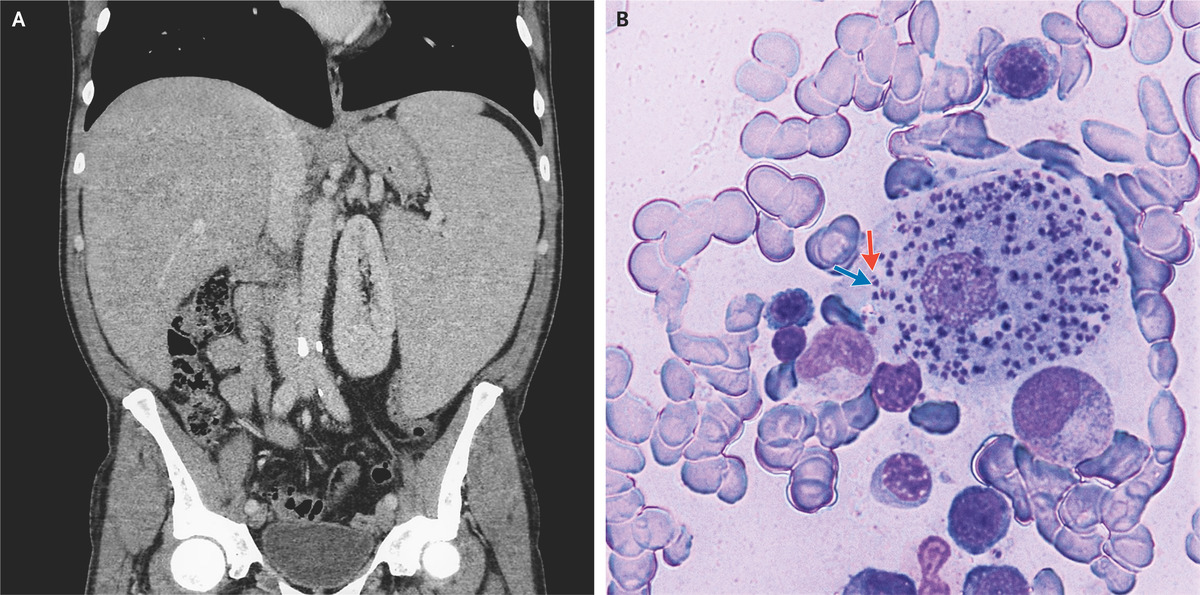

Visceral Leishmaniasis | NEJM